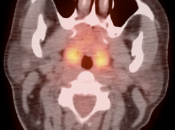

Symmetric, Bilateral Tonsillar Uptake:

The palatine tonsils frequently demonstrate significant metabolic activity.

Bilateral and fairly symmetric FDG-uptake in non-enlarged palatine tonsils is typically a normal finding, and is usually not mentioned in a report.

Bilateral and fairly symmetric FDG-uptake in enlarged palatine tonsils is nearly always inflammatory in nature (although can be seen with lymphoma).